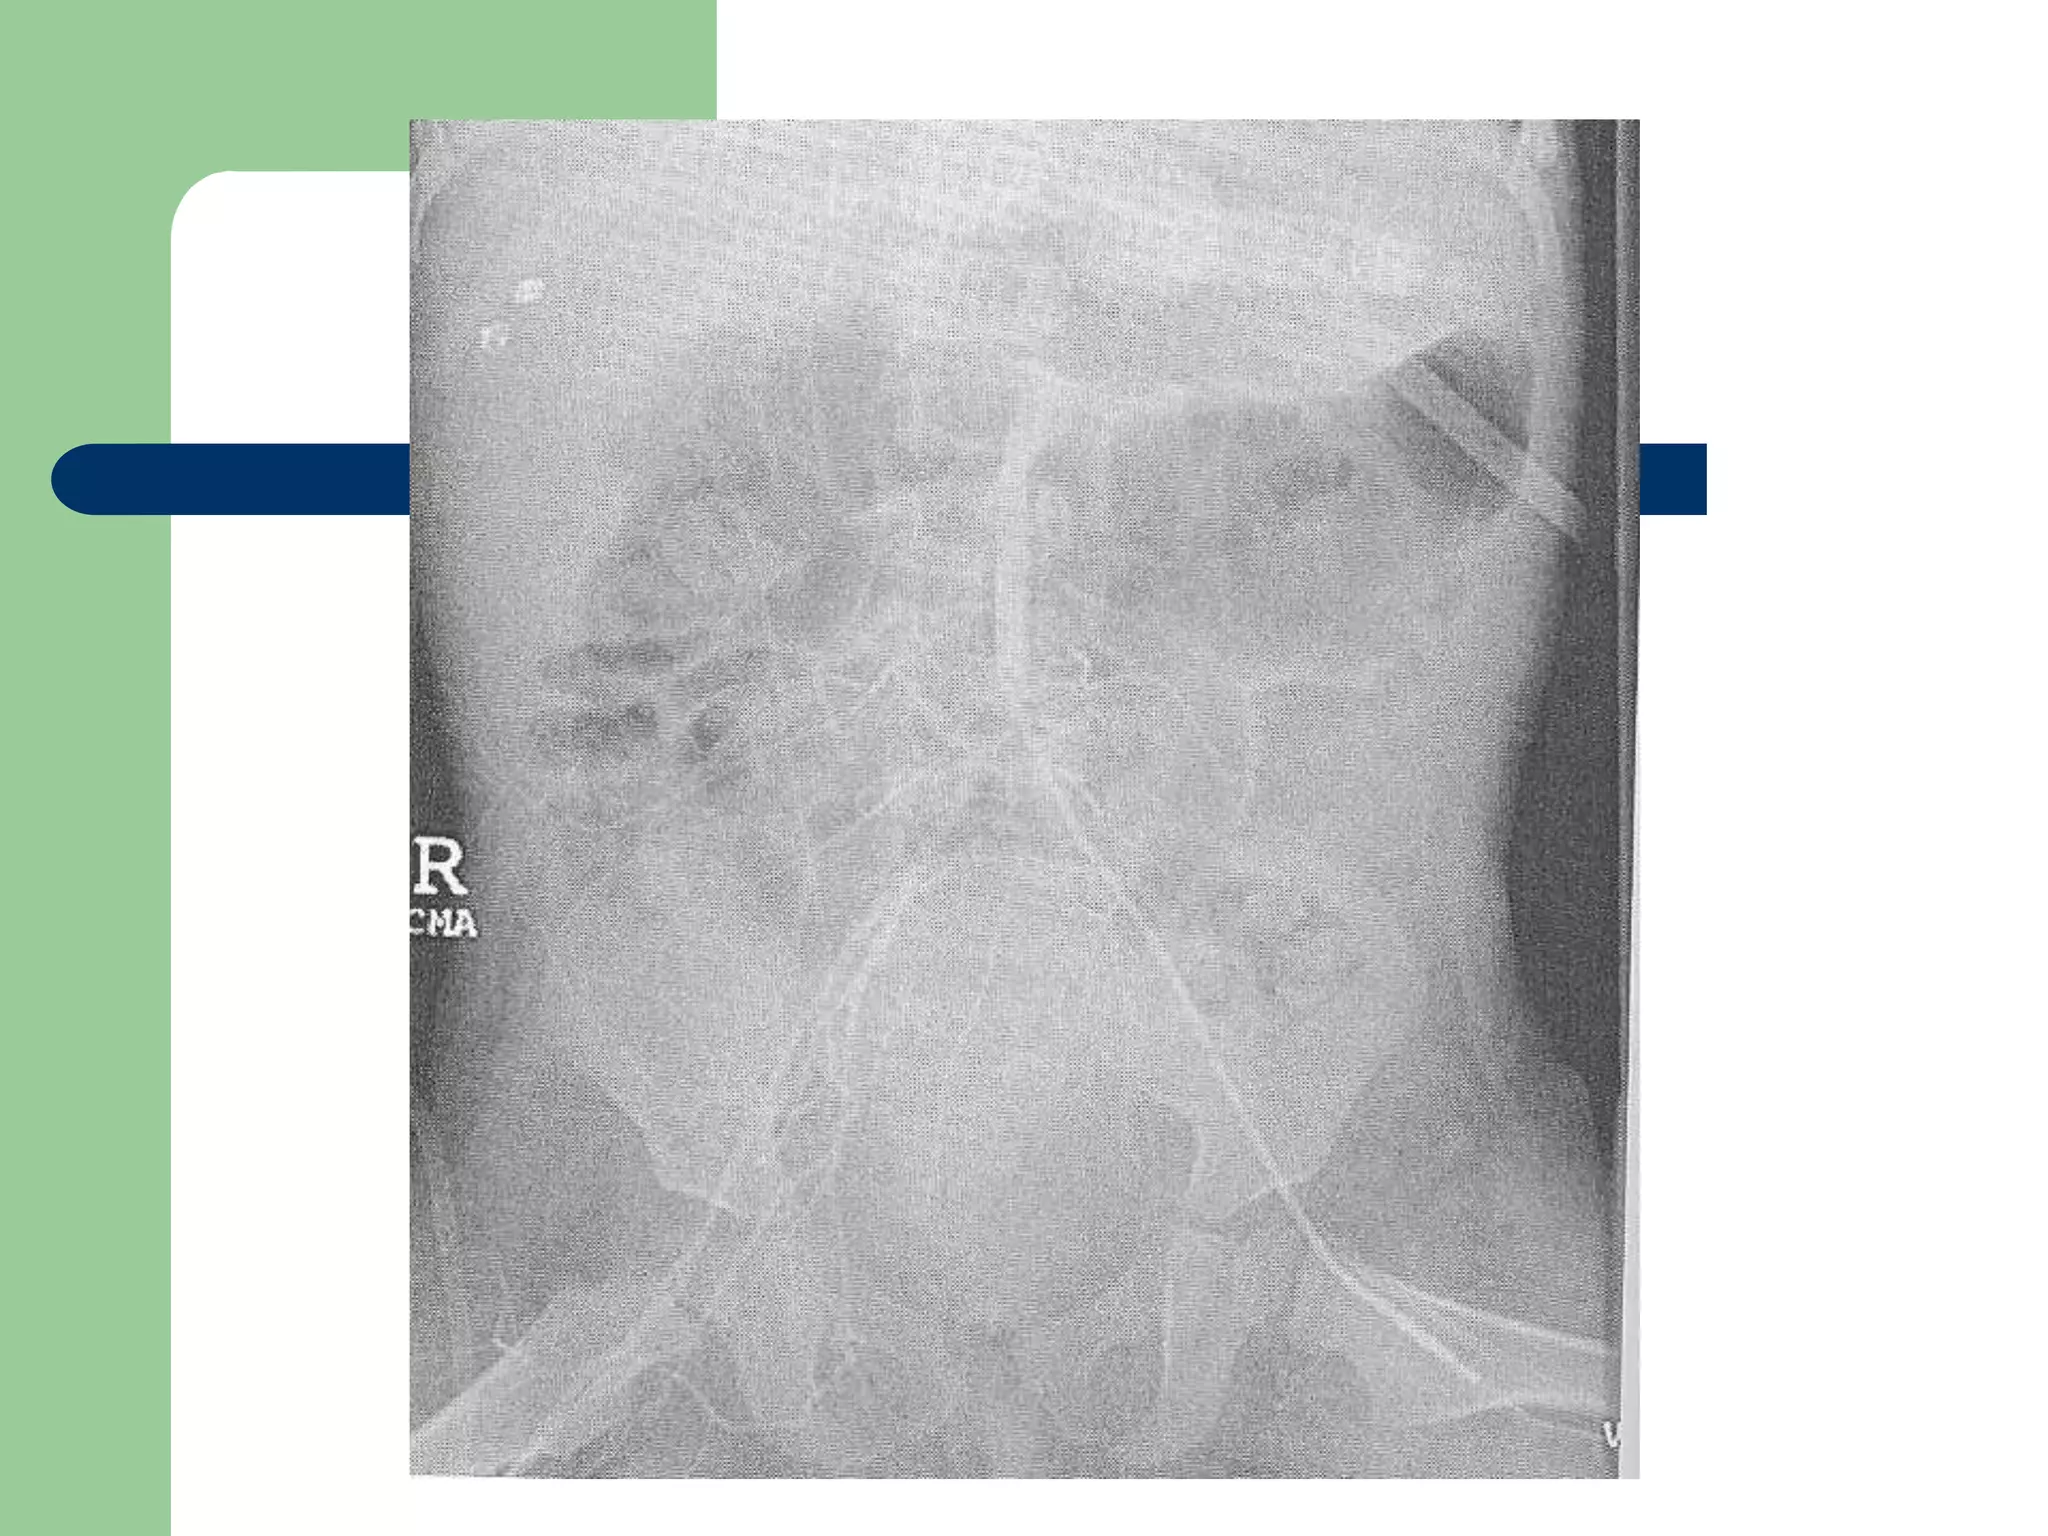

 Wheeler – “Confirmation of proper CVC

position is required after placement of all

CVC’s”

Confirmation

 Position should be in

the distal SVC

 FDA – “the catheter tip

should not be placed in

or allowed to migrate

into the heart”

 34% mortality rate with

CVC related pericardial

effusions in pediatrics